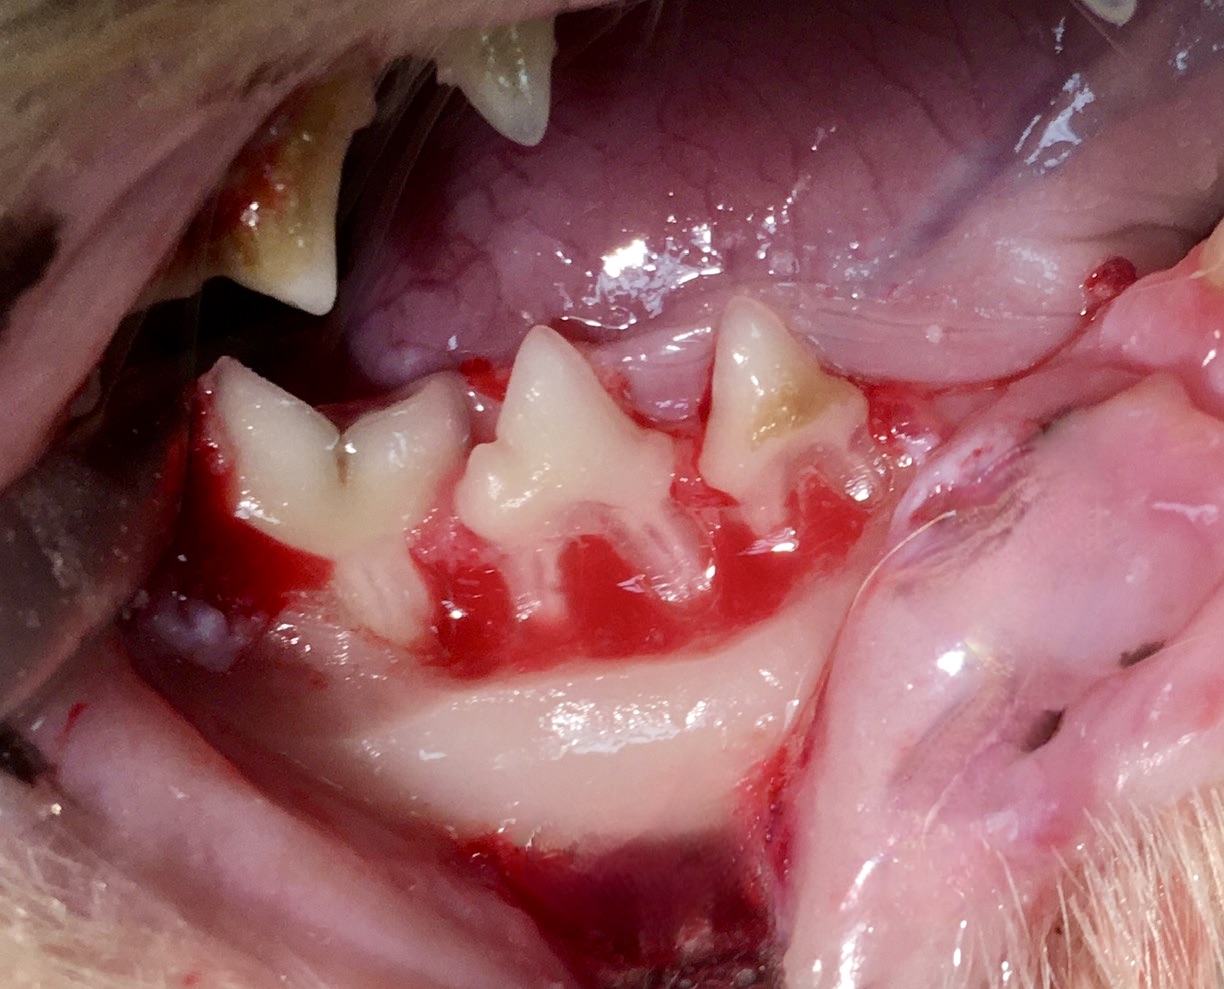

Donc… pour résumer, on va d’abord détacher la gencive de la dent, exposant ainsi l’os de la mâchoire (os alvéolaire). Celui-ci est abrasé avec une fraise sur la face externe de la dent, (on parle d’ostéotomie alvéolaire), ce qui a pour effet d’amoindrir l’ancrage des racines, vu qu’elles ne tiennent plus à l’os que par un seul côté : elles seront donc plus faciles à « luxer » pour les détacher. Les dents à plusieurs racines étant difficiles à retirer, on les découpe à la fraise en plusieurs fragments, chacun avec une seule racine : on parle de séparation radiculaire. Tout cela est en images ci-dessous.

Photo de gauche : l’os alvéolaire a été abrasé, les racines ne sont plus ancrées que d’un seul côté, et seront plus faciles à détacher, avec moins de risque qu’elles se cassent ; et si cela arrive malgré tout, le morceau cassé sera facile à repérer et à retirer ! A droite : toutes ces dents étaient à racine double et ont été découpées afin que chaque morceau ne soit plus relié qu’à une seule racine, plus facile à retirer intacte.